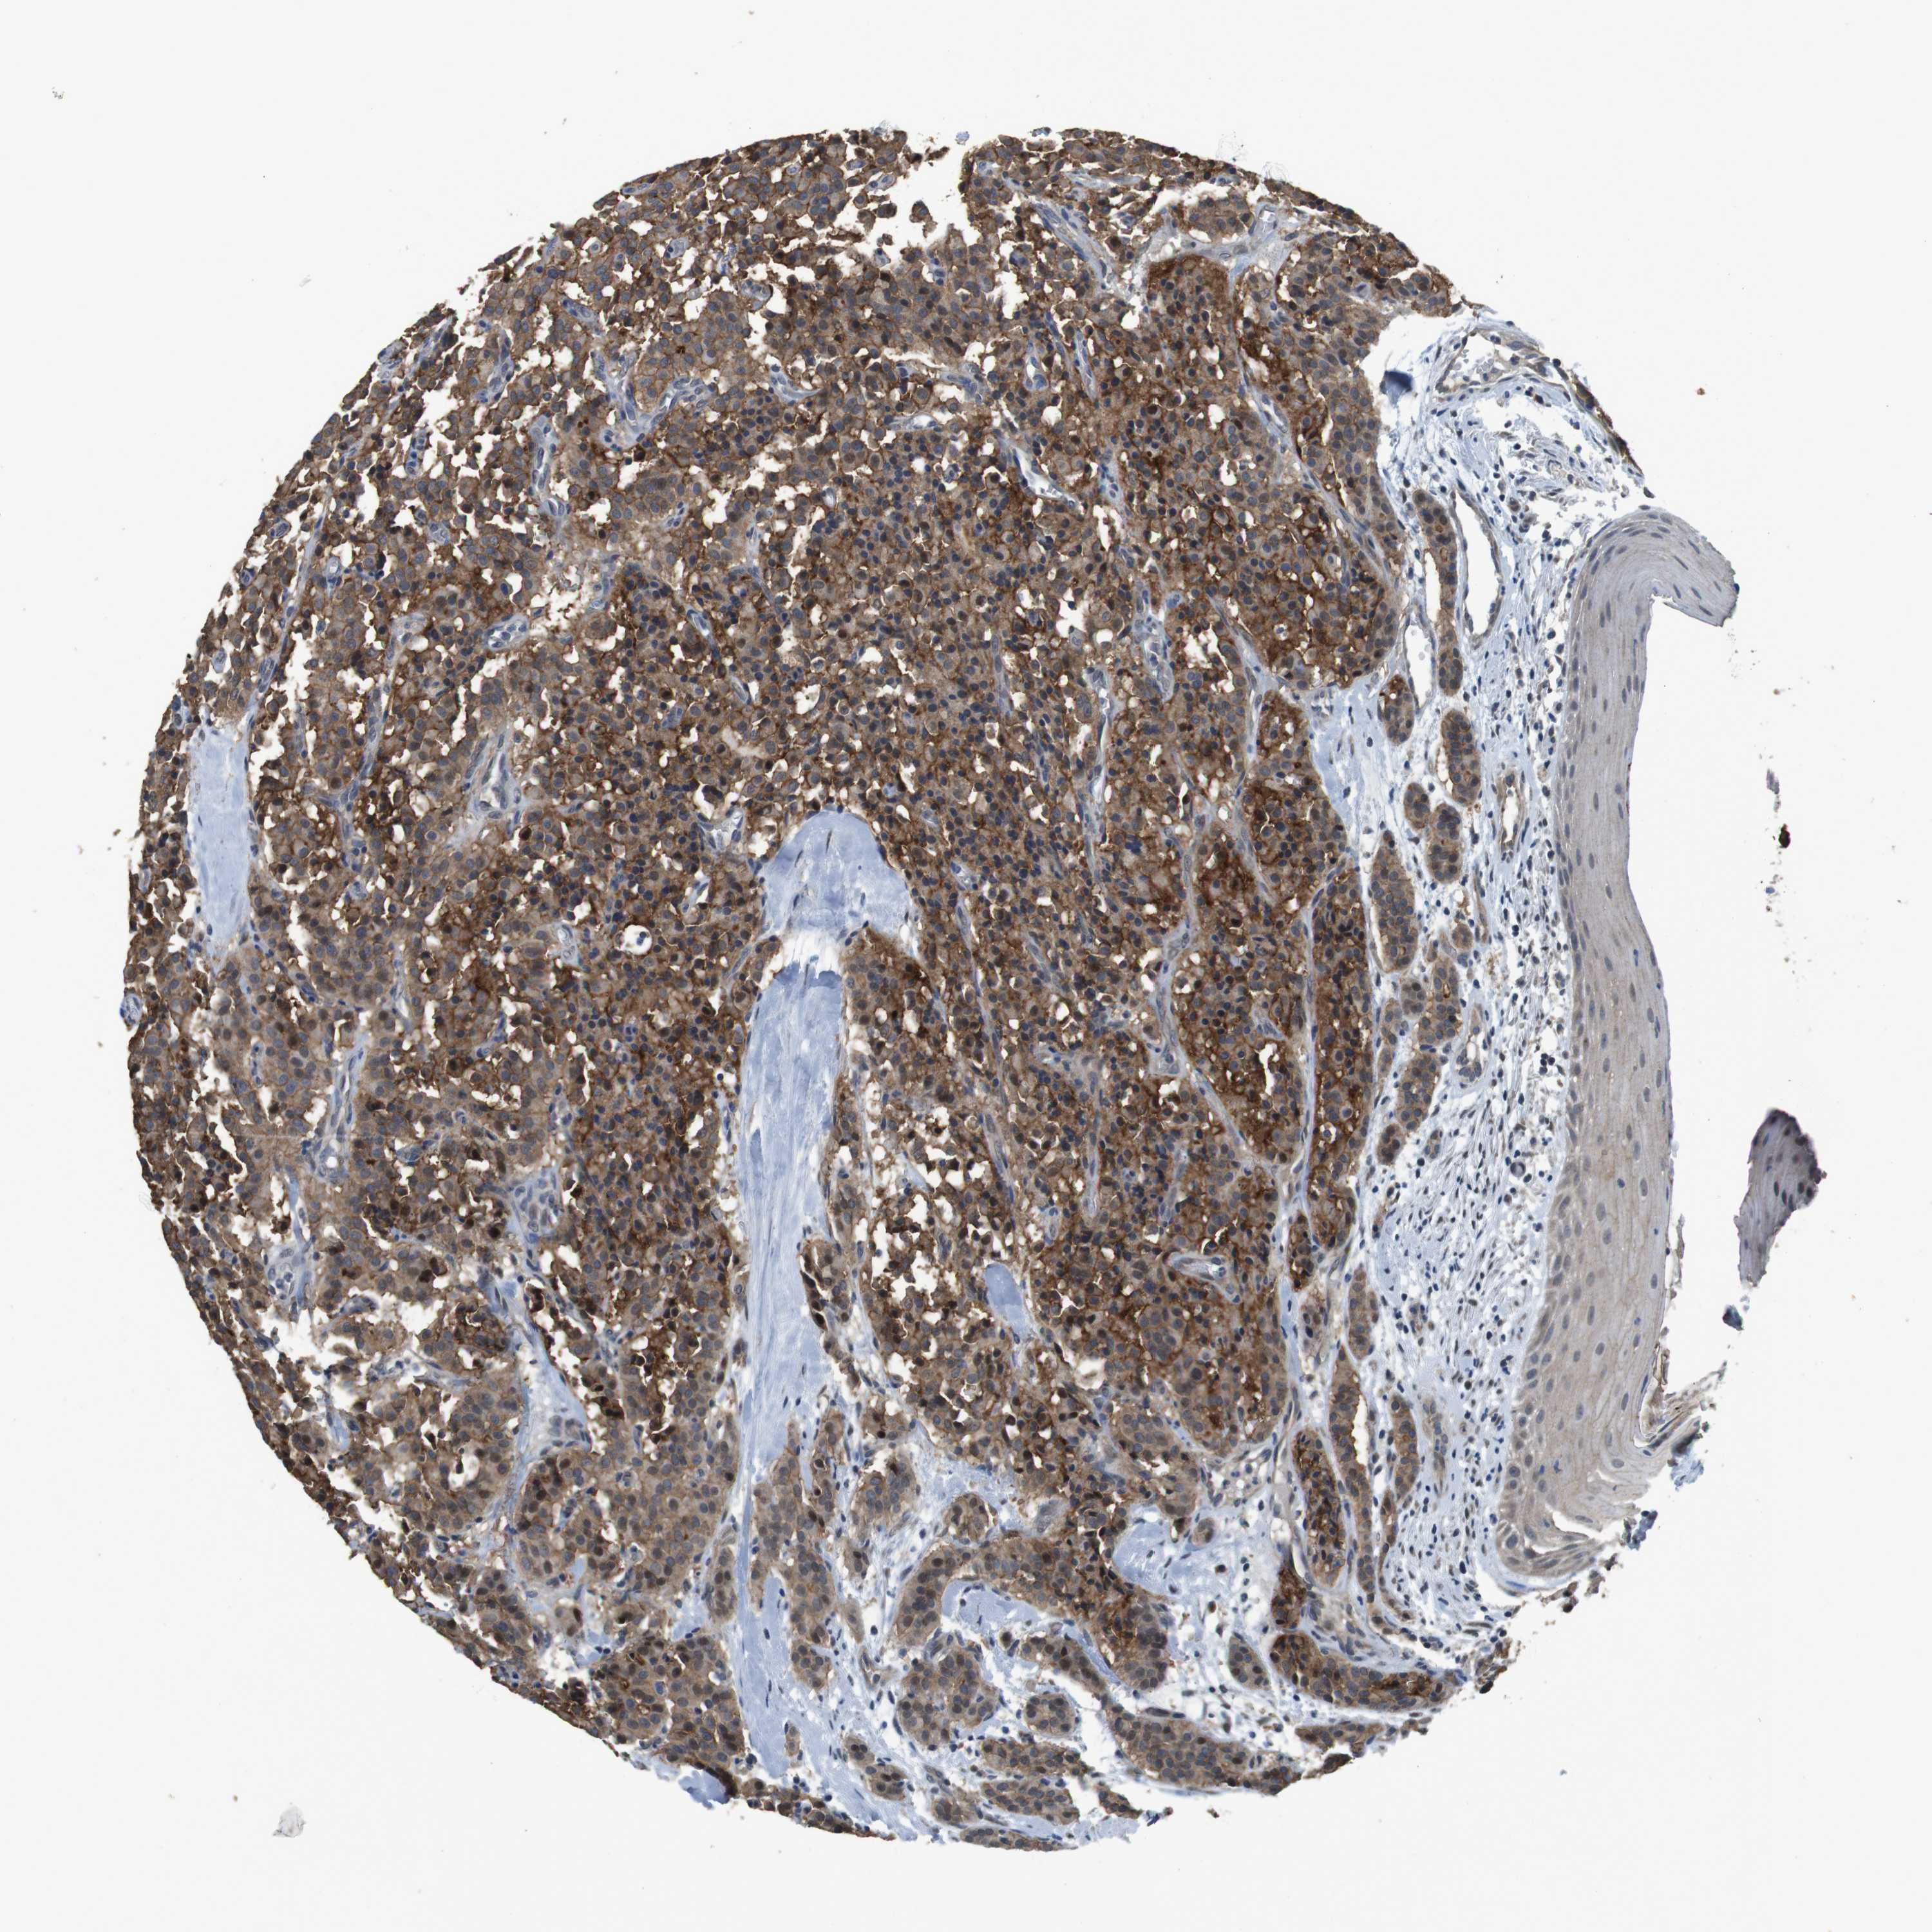

A mouse-over function shows sample information and annotation data. Click on an image to view it in a full screen mode. Samples can be filtered based on level of antibody staining by selecting one or several of the following categories: high, medium, low and not detected. The assay and annotation is described here.

Note that samples used for immunohistochemistry by the Human Protein Atlas do not correspond to samples in the TCGA dataset.

Antibody stainingi

Antibody staining in the annotated cell types in the current human tissue is reported as not detected, low, medium, or high. This score is based on the staining intensity and fraction of stained cells.